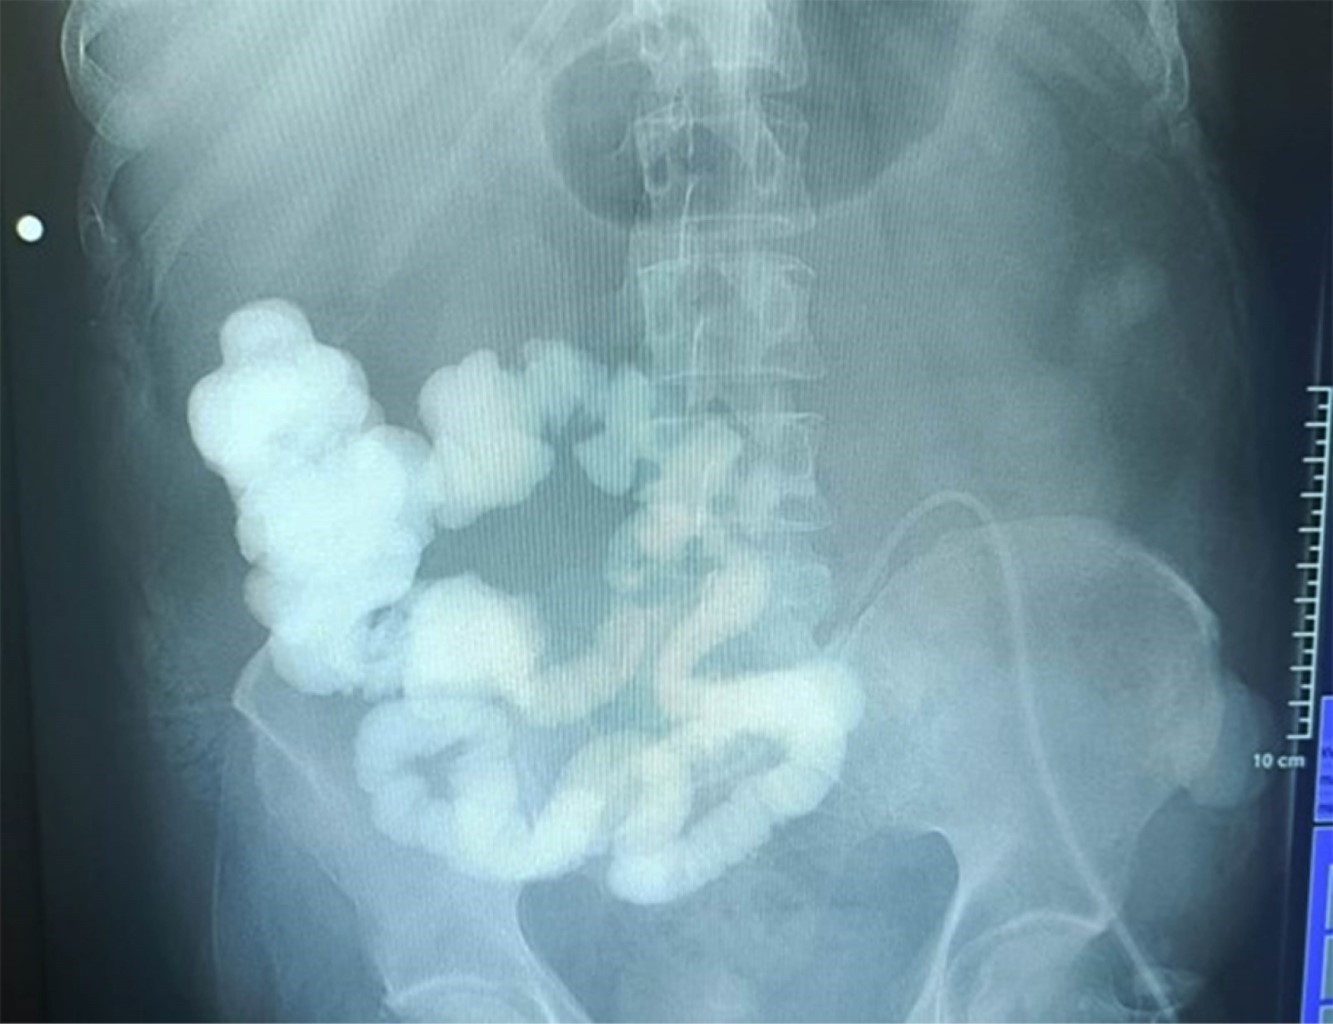

Paciente masculino de 48 años con antecedentes de poliomielitis sin secuelas aparentes durante la edad adulta. Inicia su padecimiento con abdomen agudo de causa probable apendicitis diagnosticado y atendido en hospital particular, se realiza laparoscopia con conversión a cirugía abierta, durante la cirugía se observa tumoración de yeyuno proximal (a 30 cm de ángulo de Treitz) (Figura 1), se realiza resección de 40 cm de yeyuno con anastomosis laterolateral con grapadora lineal, presentando fuga por dehiscencia de anastomosis a las 24 horas, por lo que se le realiza yeyunostomía a nivel de anastomosis, paciente con desarrollo tórpido y datos de sepsis abdominal, por lo que se envía a nuestra unidad por falta de recursos económicos.

Figura 1